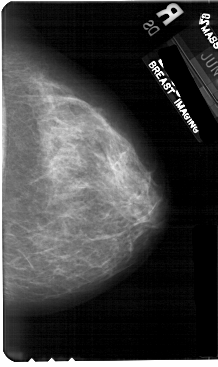

A_1725_1.LEFT_MLO

LEFT_MLO LINES 5491 PIXELS_PER_LINE 3316 BITS_PER_PIXEL 12 RESOLUTION 43.5 OVERLAY